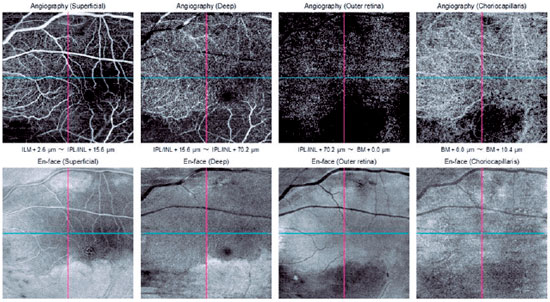

OCT-A of the right eye showed signs of normal flow and vascularization in all slabs. OCT-A of the left eye showed signs of a decrease in the superficial retinal plexus slab, except in a well-delimited band of the macular area that extended from the optic disc to the temporal macula. The same decreased blood flow was found in the deep retinal plexus slab and in the outer retinal slab. Signs of decreased flow in the choroidal slab were also found (Figure 3).

Figure 3. OCT-A of the left eye with the decreased flow sign in the superficial retinal plexus, deep retinal plexus, outer retina, and choroidal slab, with the exception of a well-delimited band of the macular area that extends from the optic disc to the temporal macula.